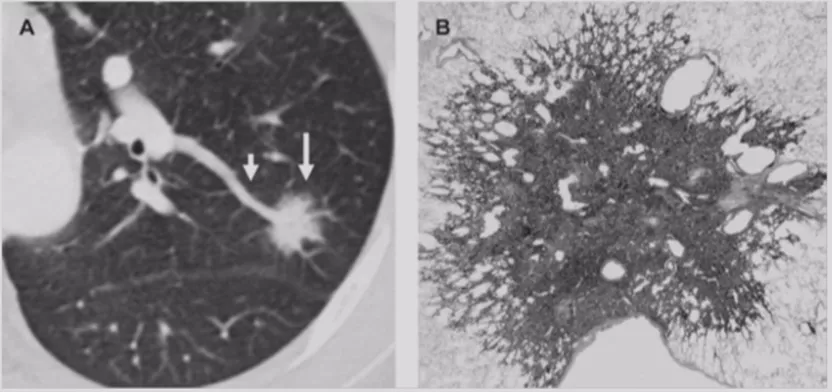

不典型腺瘤样增生(AAH)

在临床上经常手术切除后发现是AAH,关于AAH的病人是否需要手术还存在很大的争议,有的认为不需要手术,观察就可以。那么我们在术前怎么评判是否为AAH?其实具有一定特征。一般来说,多位于肺外周,多<5mm,圆形或类圆形,边界清楚,多发更常见,绝大部分是均匀的纯磨玻璃影,里边没有实性成分。组织学检查AAH呈轻度到中度非典型立方柱状上皮细胞沿肺泡和呼吸性细支气管上皮增殖,无浸润,这样在临床上诊断AAH应该没有问题。但是,如下图所示,这个病人是多灶性病变,现在多灶性结节有所增多,会给临床的处理上带来一定压力。